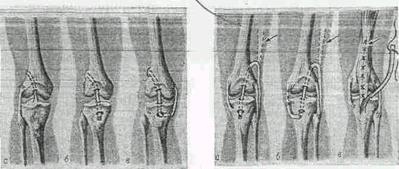

Рис 1.1. Операции на коленном суставе

Рис 1.2. Схема пластики крестообразных и боковых связок